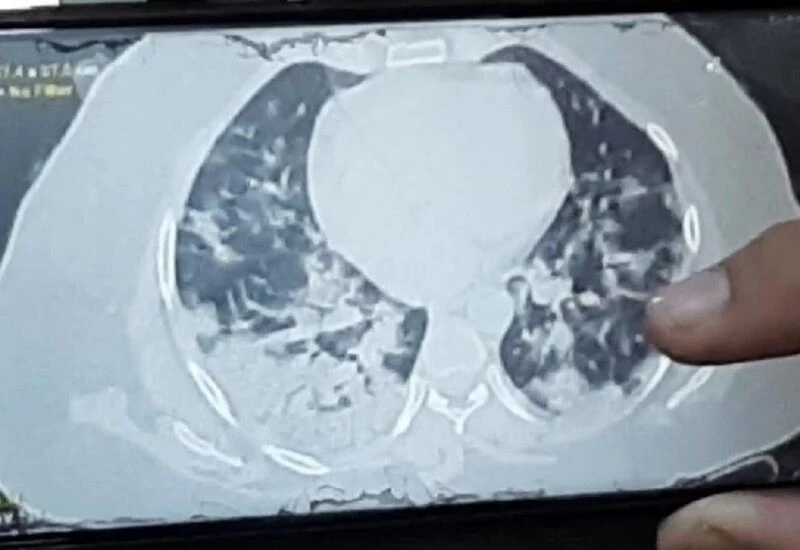

The second wave of corona virus has created panic. Meanwhile, a terrible case has come out of Kota city of Rajasthan, where both the lungs of a 32-year-old woman got damaged in 24 hours. Pictures of this have also surfaced. Actually, this is the case of Kota, if a 32-year-old woman got an X-ray done on the 9th, she was fine, even on the 12th, that woman was fine. BP, oxygen level, x ray all was well. This was followed by a nervous feeling on the night of the 12th.

The woman could not even stand on the 13th, having difficulty breathing, after checking, it was found that the oxygen level was 94. When the city was scanned on the 13th, both of its langs had been infected up to 80 percent.

Seeing this, Kota's health expert Dr. KK Dung was also surprised that langs could be so bad in just 24 hours. When he consulted the expert doctor of Indore, he told that this is the new strain due to which it has happened.

The doctor says that this new strain is spreading rapidly, it is also spreading lung infection very rapidly among the youth. We should take a lesson from this case and investigate as soon as symptoms appear, because Corona is not giving time now. In spite of BP oxygen level X ray all is well, there can be infection in very langs.